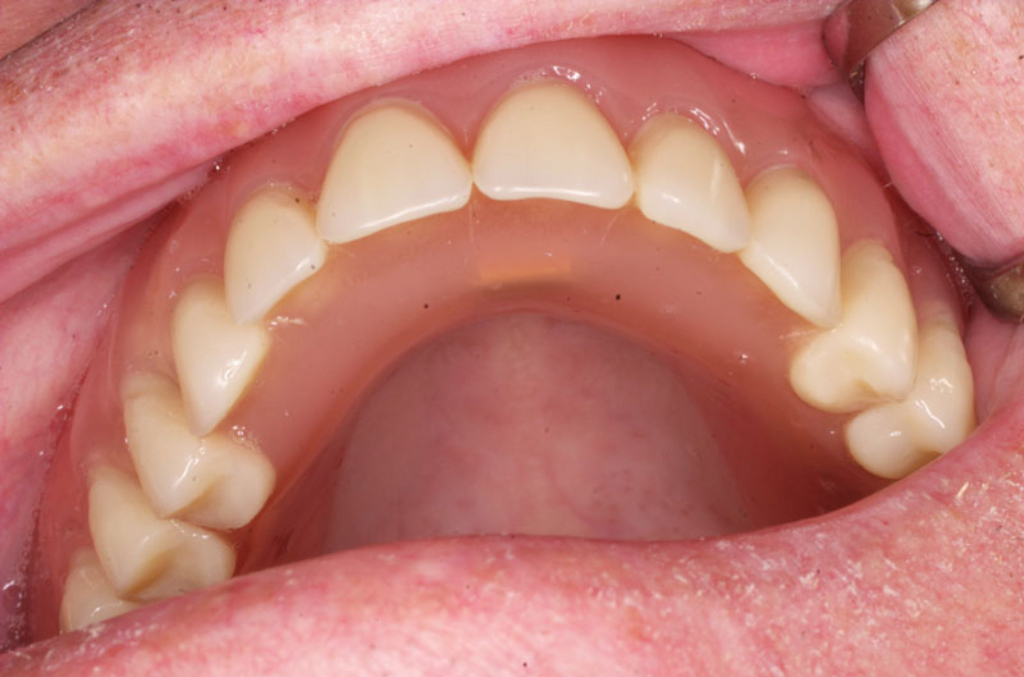

Pevné můstky – lepené nebo šroubované

Třmeny

Kulové attachmenty

Sub-Tec Locator®

Metoda All-on-four

S pomocí zubních implantátů můžeme díky různým kotevním systémům (třmeny, kulové hlavy, Locatory) zajistit stabilitu a držení protézy nebo při použití většího počtu implantátů zhotovit pevné náhrady – můstky nalepené nebo našroubované na pevno na implantáty.

S těmito typy náhrad můžeme dosáhnout perfektní funkci, výbornou estetiku, fonetiku a současně zajistit u pacienta možnost dobré hygienickou péče a čištění, která je pro životnost implantátů velice důležitá.